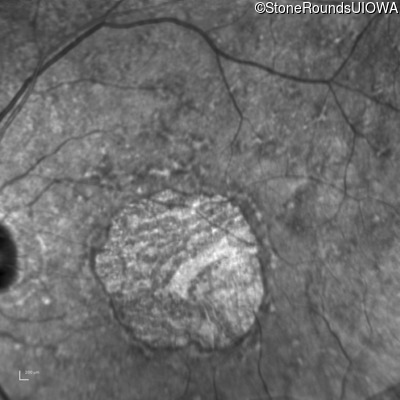

Fluorescein Angiography - Right - 20/70

Exemplar